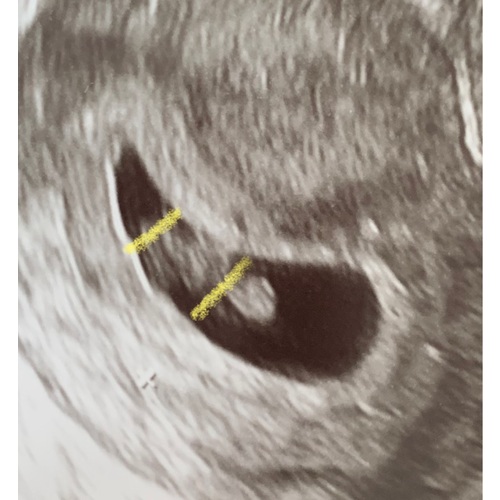

Inwendige echo: Zie je op de uitdraai van een inwendige echo de lichte vlek rechts in de baarmoeder? Dan verwacht je volgens de Ramzi-theorie een jongen. Wanneer je hem links in de baarmoeder ziet, zou je van een meisje in verwachting zijn.

Uitwendige echo: Als de echo via je buik is gemaakt, is de echo gespiegeld. Zie je op de uitdraai van de echo de lichte vlek rechts? Dan zou dit betekenen dat je een meisje krijgt. Een lichte vlek aan de linkerkant wijst bij een uitwendige echo op een jongen.

Dit is dan het model voor een uitwendige echo ! Inwendig is het andersom

Oke dan ben ik heel erg benieuwd wat dit dan eventueel kan zijn volgens de ramzi methode dit is een inwendige echo geweest bij 8 weken zwangerschap